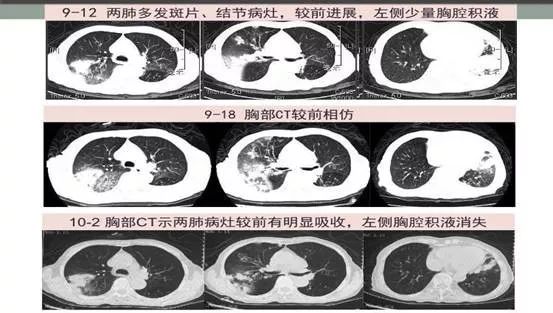

男56岁,发热咳嗽咳痰23天。肺部CT变化见下图:

痰培养(3-7天):烟曲霉,mNGS:(48小时):烟曲霉。给予伏立康唑静滴+两性霉素B雾化吸入+糖皮质激素抗炎。起始卡泊芬净联合治疗12天,好转出院。